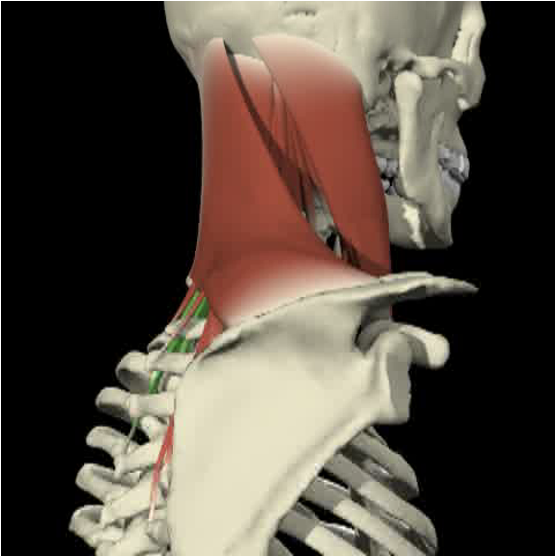

Splenius Capitis

Anatomy

Splenius capitis forms part of the floor of the posterior triangle of the neck, above and behind levator scapulae; it is deep to the rhomboideus and trapezius.

- Origin

-

- It is attached proximally to the lower half of the ligamentum nuchae, spinous processes of C7 to T4 and intervening supraspinous ligaments.

- Insertion

Action

- Individually

- Extends the head and neck, accompanied by lateral flexion of the neck and rotation of the face to the same side.

- Together

- Pure extension

Splenius Capitis/Cervicis

- Midway between the inion and mastoid process

- From the same attachment forward is SCM

- Runs obliquely to spinal processes of C7 to T3

- Cervicis runs lateral border and underneath capitus anterior to levator scapulae.

Surface Anatomy